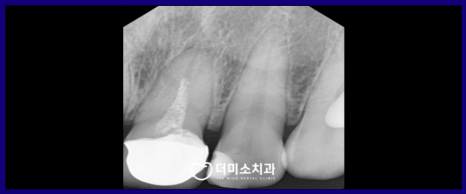

먼저 구강 내를 확인해 보았더니

위턱 왼쪽 첫 번째 앞니(#21)에

약간의 잇몸 퇴축도 있었으며

잇몸 라인이 까맣게 비춰 보이는 것을

확인할 수 있었는데요.

정밀한 검사를 위해

파노라마 사진과 X-ray 사진을

촬영해 보았더니

신경치료 후 채워 넣는 치과 재료가

뿌리 끝까지 꼼꼼하게 채워지지 않은

불완전 근관치료 상태인 것을

이 경우 재신경치료가

필요한 상황이었습니다.